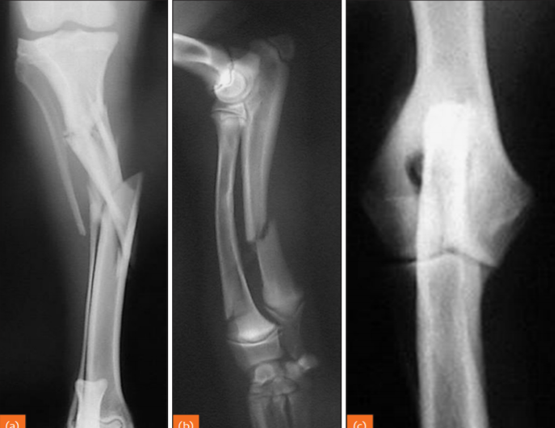

identify left to right

A

left to right:

Transverse fracture

Oblique fracture

Spiral fracture

How well did you know this?